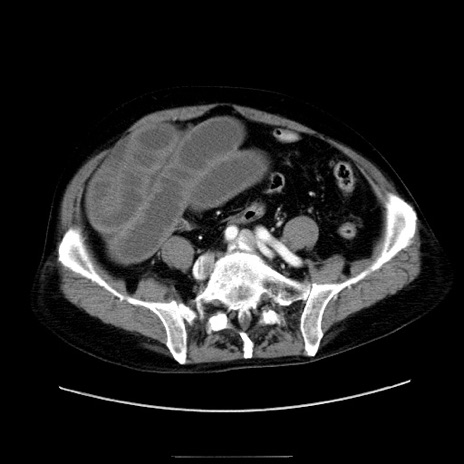

症例30(横断像)

【症例】80歳代男性

【現病歴】約6時間前から臍下部痛が出現。次第に腹部膨隆・背部痛も生じてきたため来院。背部痛の場所は変化しない。

【身体所見】意識清明、BT 36.3℃、BP  131/87mmHg、P 87bpm、SpO2 100%(RA)、臍周囲自発痛・圧痛あり、反跳痛なし、自発痛部位に一致して板状硬あり、腹部膨隆、腸雑音減弱、CVA tenderness両側陰性。